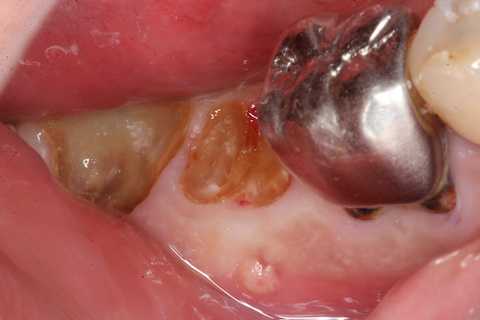

今日も野戦病院シリーズ26(CK破折) 2025.10.25